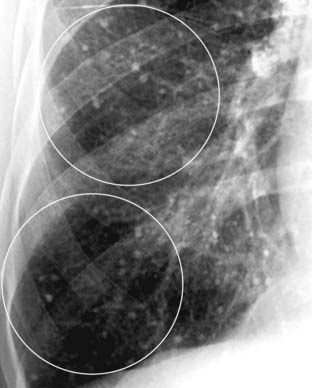

Figure 3-8 The patterns of interstitial lung disease.

A, The disease is primarily reticular in nature, consisting of crisscrossing lines (solid white circle). This patient had advanced sarcoidosis. B, The disease is predominantly nodular (dotted white circle). The patient was known to have thyroid carcinoma, and these nodules represent innumerable small metastatic foci in the lungs. C, Interstitial disease of the lung, reticulonodular. Most interstitial diseases of the lung have a mixture of both a reticular (lines) and nodular (dots) pattern, as does this case, which is a close-up view of the right lower lobe in another patient with sarcoidosis. The disease (dashed white circle) consists of both an intersecting, lacy network of lines and small nodules.

These “particles” of disease can be further characterized as having three patterns of presentation:

image Reticular interstitial disease appears as a network of lines (see Fig. 3-8A).

image Nodular interstitial disease appears as an assortment of dots (see Fig. 3-8B).

image Reticulonodular interstitial disease contains both lines and dots (see Fig. 3-8C).